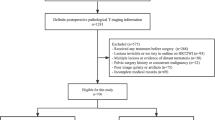

We included 39 patients (men: women, 21:18; mean age ± standard deviation, 59.1 ± 9.7 years) with mid-to-lower rectal cancer who underwent a long-course of CRT and high-resolution rectal MRIs between January 2020 and April 2021. Axial T2WI was reconstructed using the conventional method (MRIconv) and DLR with two different noise reduction factors (MRIDLR30 and MRIDLR50). The signal-to-noise ratio (SNR) of the tumor was measured. Two experienced radiologists independently made a blind assessment of the complete response on MRI. The sensitivity and specificity for pCR were analyzed using a multivariable logistic regression analysis with generalized estimating equations.